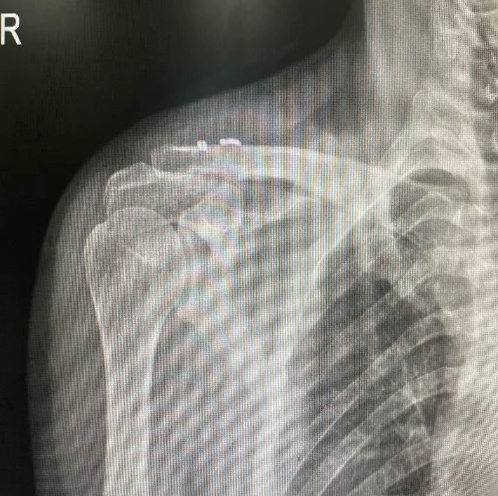

患者黄某,因骑车摔倒致右肩锁关节脱位,术前畸形明显、疼痛剧烈。术后次日即开始被动活动,疼痛显著下降,第3天出院,肩部外形恢复正常,对微创效果非常满意。

术后